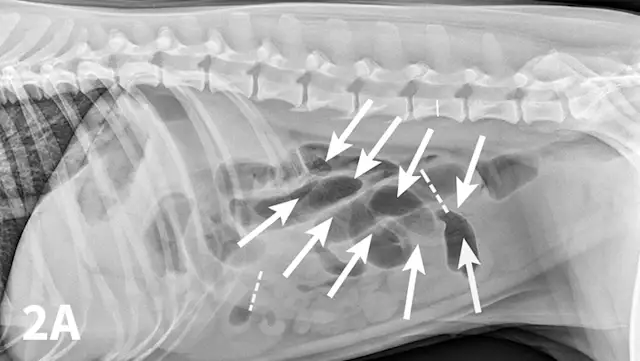

Radiographic features of small intestinal mechanical obstruction depend on its completeness, location, and duration.2 Whereas metallic FBs or those with mineral content are easily recognized within the GI lumen (Figure 1), nonmineralized, nonmetallic objects (eg, cloth) within the GI tract are more difficult to identify (Figure 2). Some may be recognized by their geometric shape. The most consistent sign of mechanical obstruction is variable dilation of intestinal loops proximal (orad) to the obstruction (described as a mixed population of small intestine; Figure 2). Determination of small intestinal diameter can be made by comparing it to the L5 vertebral body height in dogs.3 Values greater than 1.6 are suggestive of obstruction (Figure 2A). In cats, a ratio of the maximum small intestinal diameter to vertebral end plate height of L2 greater than 4 indicates a high likelihood of intestinal obstruction.4

Right lateral (A) and VD (B) abdominal radiographs of a Labrador retriever with an obstructive ileus. A FB (sock) is present within a dilated small intestinal loop in the right caudoventral abdomen (arrows). The dashed lines outline a fluid-filled loop measuring 2.7 cm and a gas-filled loop measuring 2.4 cm, compared to the height of L5 (Asolid line, 1.1 cm);  the resulting ratios of 2.4 and 2.2, respectively, are much greater than the upper limit of 1.6 for normal small intestine to L5 height ratio. Several stacked gas-filled loops of small intestine are present in the left midabdomen (B).